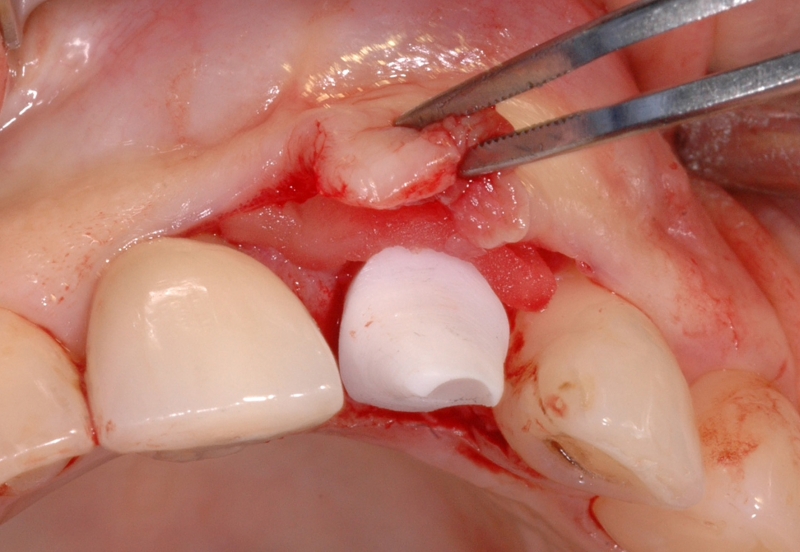

13/18 - Further soft tissue augmentation with mucoderm®GBR together with soft tissue augmentation with mucoderm® and maxresorb® - Dr. S. Scherg